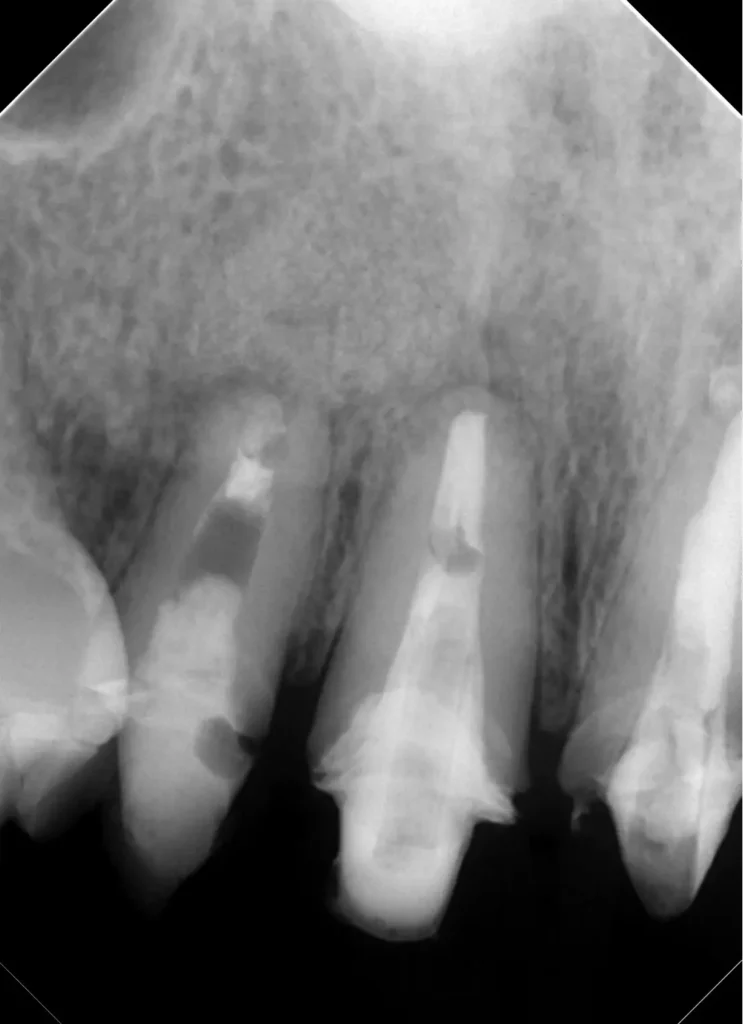

自費根管治療症例4 治療前(外科的歯内療法)

「前歯にニキビみたいなものができた」

初診時

離れていますが真ん中が原因歯です

初診時レントゲン写真

治療はしてありますが、根の先が黒ずんで見えます

CT画像

唇側の顎骨が溶けて穴が空いています